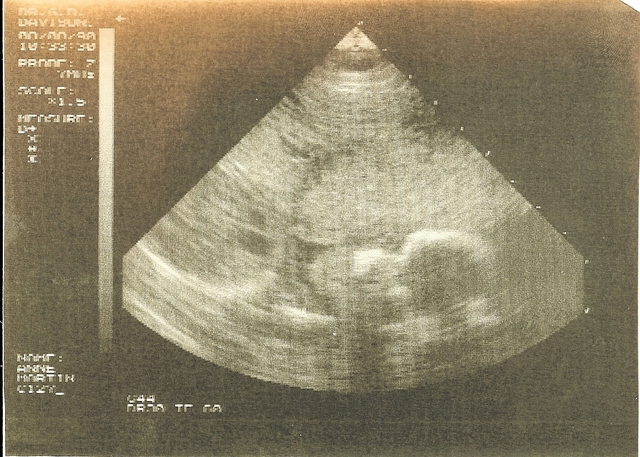

An ultrasound showing me before I was born and before I was Stephanie.